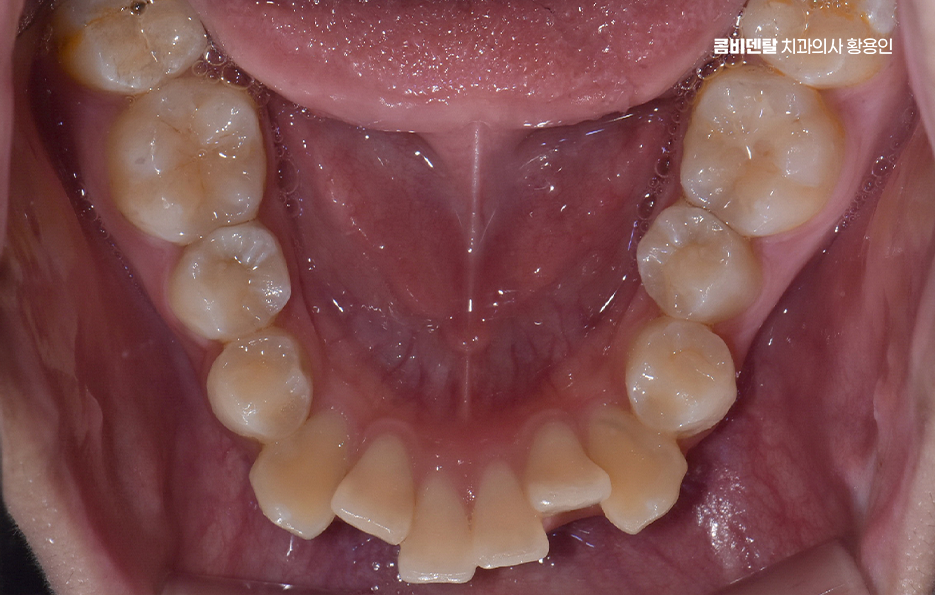

특히 교합이 틀어진 상태에서는 특정 치아에만 씹는 힘이 과도하게 실리게 되는데 이로 인해 일부 치아는 빠르게 마모되거나 깨지게 되고, 반대로 거의 사용되지 않는 치아는 치주 조직이 약해져서 잇몸 퇴축이나 치주염이 생길 확률도 높아지는 거예요. 그리고 치열이 고르지 않은 상태에서는 양치질을 꼼꼼히 해도 치간이나 치아 뒷면에 음식물과 세균이 남기 쉬워서 충치 발생률도 높아지는 건 당연한 것이며 결국 부정교합은 기능적인 저작 문제, 치아의 수명 단축, 잇몸 질환이라는 복합적인 문제로 이어지게 될 수 있어요

그렇다면 이런 부정교합 문제를 해결하기 위해선 어떤 방식으로 치료계획을 세워야 하느냐가 중요한데 첫 번째 단계는 정밀한 진단과 분석으로 단순히 눈으로 보기엔 어느정도 가지런해 보여도 실제로는 턱의 중심선이 틀어져 있거나, 치아의 경사가 비정상적으로 되어 있을 수 있기 때문에 파노라마 X-ray, 세팔로, 구강 스캐너, 3D CT 등을 통해 턱의 구조, 치아 배열, 뼈 상태 등을 면밀히 분석해야 정확한 치료계획이 세워지는 거예요.

이때 골격적인 문제인지, 치아 배열만의 문제인지에 따라 발치 여부, 교정 방식, 치료 기간이 달라지고 연령 대에 따라선 성장기인지 성인인지에 따라서도 적용할 수 있는 교정 계획이 달라지고 있었어요